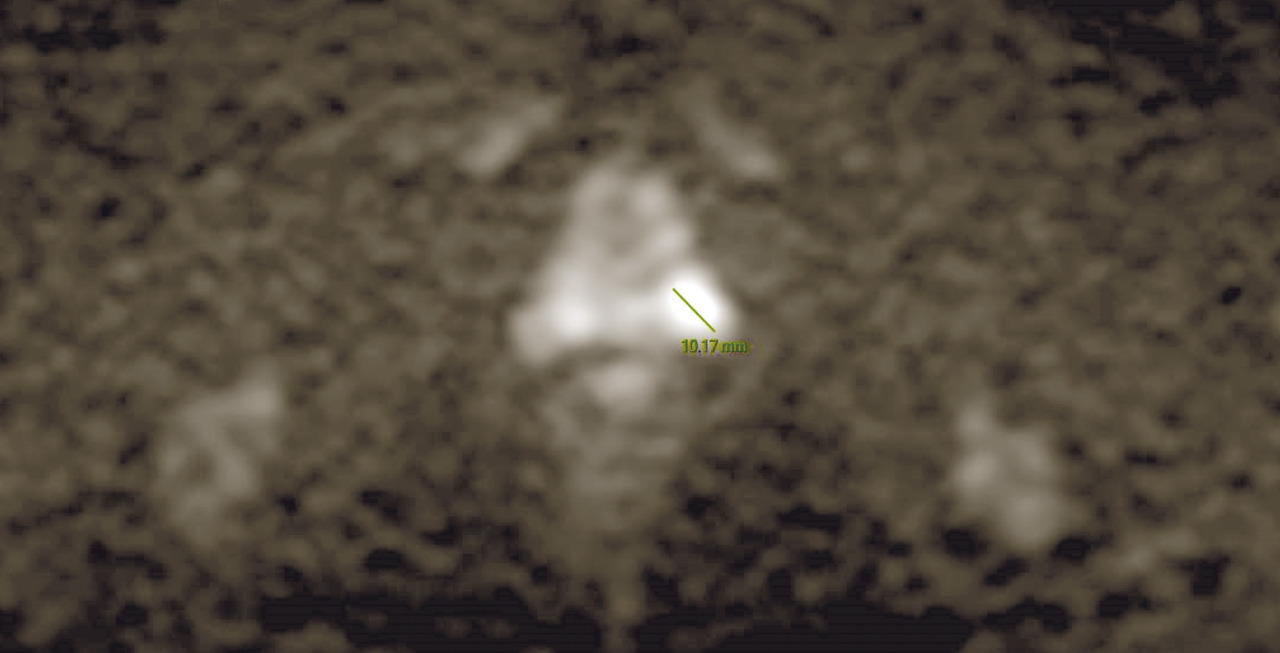

À ce jour, avec la diffusion d’outils de plus en plus sophistiqués et précis pour effectuer des biopsies avec fusion d’images entre l’IRM multiparamétrique et l’échographie transrectale en temps réel, la biopsie avec connaissance de l’anatomie prostatique sur la base des images d’IRM réalisée sous guidage échographique est devenue une approche indispensable, permettant de faire évoluer les biopsies systématisées, réalisées « à l’aveugle», vers des biopsies ciblées. De nombreuses études ont montré que l’échantillonnage ciblé, en plus de l’approche systématique, est mieux corrélé au score de Gleason pathologique, tandis que d’autres ont montré une meilleure performance en termes de sensibilité et de spécificité de la biopsie ciblée par rapport à la réalisation des biopsies avec approche systématique, réduisant de manière significative le taux de détection des tumeurs cliniquement non significatives. Par conséquent, la réalisation de l’IRM avant de programmer les biopsies est de plus en plus recommandée afin de :

- poser l’indication à la biopsie en cas de détection de lésions significatives ;

- permettre la surveillance du patient en cas d’absence de lésions significatives ;

- guider l’échantillonnage des biopsies de la région cible.

La biopsie par schéma en sextant n’étant plus adéquate, un nombre plus élevé d’échantillons est considéré comme nécessaire, généralement entre 8 et 12, en plus de toute biopsie ciblée des lésions visibles identifiées à l’IRM. Le choix de la voie d’accès ne semble pas affecter la sensibilité et la spécificité de la méthode, même si la voie transpérinéale est connue pour avoir une sensibilité majeure par rapport à la voie transrectale. En cas de suspicion clinique d’extension extracapsulaire (extraprostatique), la cartographie peut être étendue aux vésicules séminales et au tissu périprostatique. Cependant, au-delà de ces indications spécifiques, il faut souligner qu’aucune preuve scientifique ne montre que l’augmentation du diagnostic de carcinome attribuable à l’augmentation de l’échantillonnage offre un réel avantage au patient : il n’est pas prouvé, en fait, que l’augmentation du nombre des biopsies ait une meilleure capacité à diagnostiquer des cancers agressifs autrement non diagnostiqués. En revanche, il est très probable qu’une bonne partie des cancers « supplémentaires », diagnostiqués en augmentant le nombre de biopsies, soit, en fait, non agressive et destinée à ne pas évoluer. En ce sens, l’information fournie au préalable par l’IRM, par rapport à sa capacité à identifier des zones plus à risque de contenir des cancers réellement significatifs, semble être le seul outil pour remédier à ce problème.